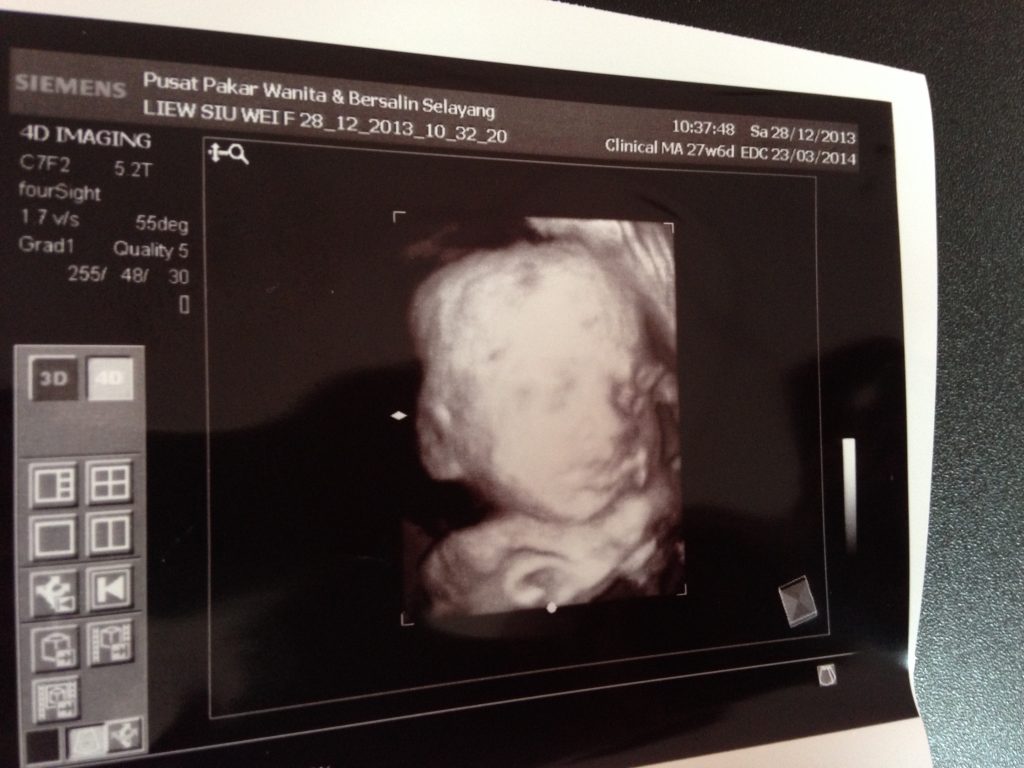

My breastfeeding memory